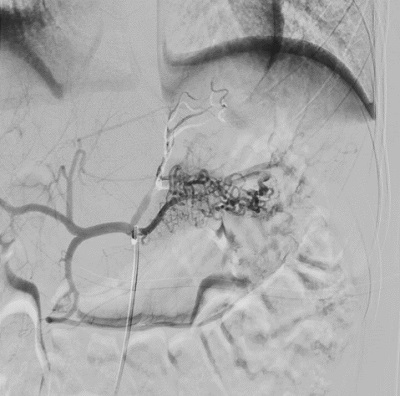

En el episodio actual, acudió a Urgencias por un episodio de hematemesis, melenas y síncope que precisó en dos ocasiones la administración de suero salino fisiológico 0,9% a 20 ml/kg e ingreso en UCIP para vigilancia. Presentó una anemización progresiva hasta hemoglobina de 6,9 g/dl, precisando transfusión de dos concentrados de hematíes. Durante su ingreso se realizó ecografía abdominal y gastroscopia sin alteraciones significativas y valoración por Otorrinolaringología descartando foco del sangrado a dicho nivel. Al tercer día de ingreso, se realizó angiografía mostrando una malformación vascular de tipo arterial en región fúndico-cardial en aspecto de “ovillo”.

Ante dichos hallazgos se decidió traslado a nuestro centro, donde se realizó una arteriografía diagnóstico-terapéutica. La embolización de la malformación transcurrió sin incidencias (Figs. 1 y 2).

| Figura 1. Malformación arterial gastropancreática con aspecto de ovillo. Irrigación principal a expensas de arteria gástrica izquierda y arteria esplénica. El componente gástrico se comporta como una lesión de Dieulafoy |